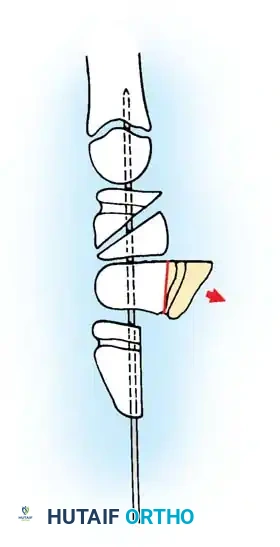

Anatomical diagram illustrating the mismatch between the hypertrophied intratendinous nodule and the stenotic A1 pulley.

Intraoperative visualization of the flexor tendon sheath, highlighting the critical relationship between the A1 and A2 pulleys.

Intraoperative view demonstrating the excision of an abnormal FDS slip to relieve persistent triggering after A1 release.